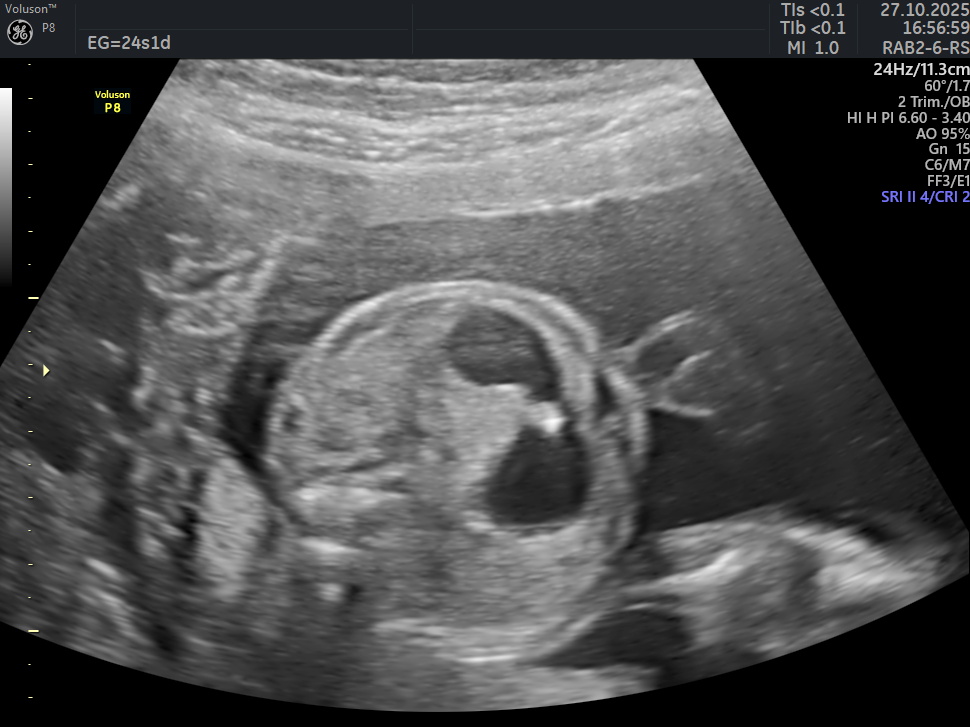

Se presenta el caso de una paciente de 39 años de edad, primigesta, sin antecedentes personales ni familiares de relevancia. La paciente adjunta el estudio de screening de aneuploidías de la semana 11-14, que arroja bajo riesgo. Las imágenes que se presentan a continuación corresponden al estudio morfológico fetal realizado en la semana 24. Seleccione la opción correcta : A. Se visualiza cámara gástrica dilatada, conectada con una imagen quística anecogénica, de probable origen duodenal (Signo de la doble burbuja). B. La anatomía es de apariencia normal para la edad gestacional. C. Los hallazgos podrían corresponder a una probable atresia esofágica. D. Los hallazgos podrían corresponder a una dilatación quística del conducto biliar.